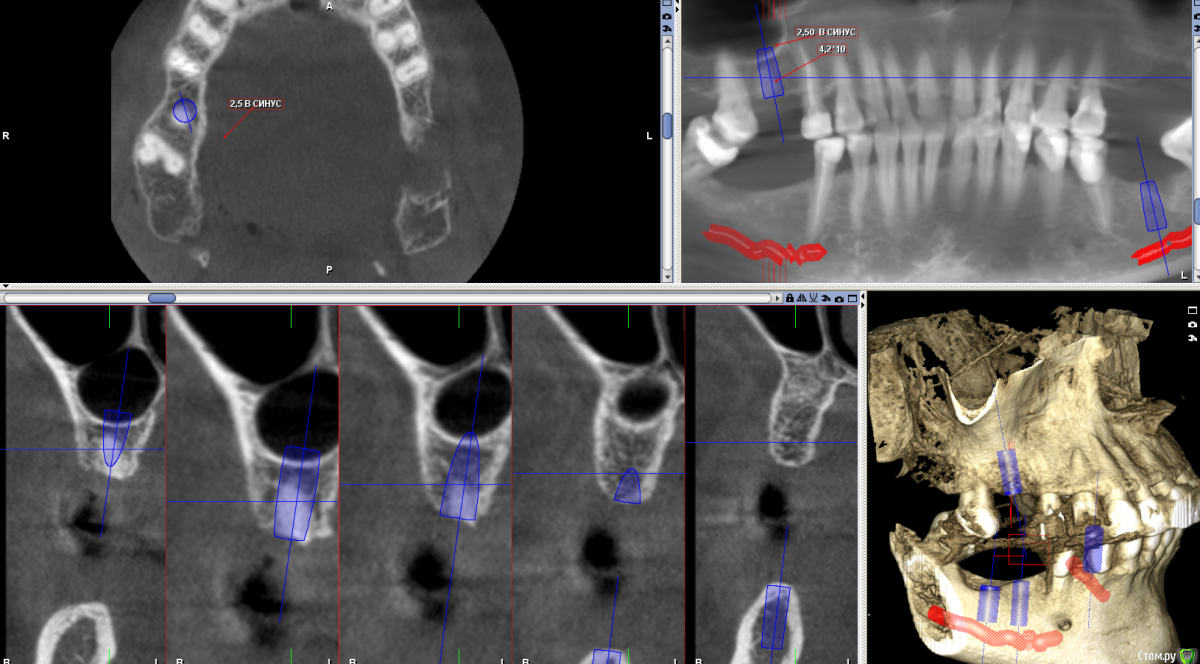

Sergiosse Опубликовано 20 января, 2016 Поделиться Опубликовано 20 января, 2016 Планируется установка 3 - х имплантов .В обл. 16 зуба 4,2х10мм ,на 2,5мм выходит в синус.Планирую подломить стенку остеотомом и вкрутить. В обл 26зуба 4,2х8мм.тоже самое. А с 27 что делать? Зуб удален 2.5 мес. назад.Посоветуйте, как поступить? Заранее спасибо. Ссылка на комментарий